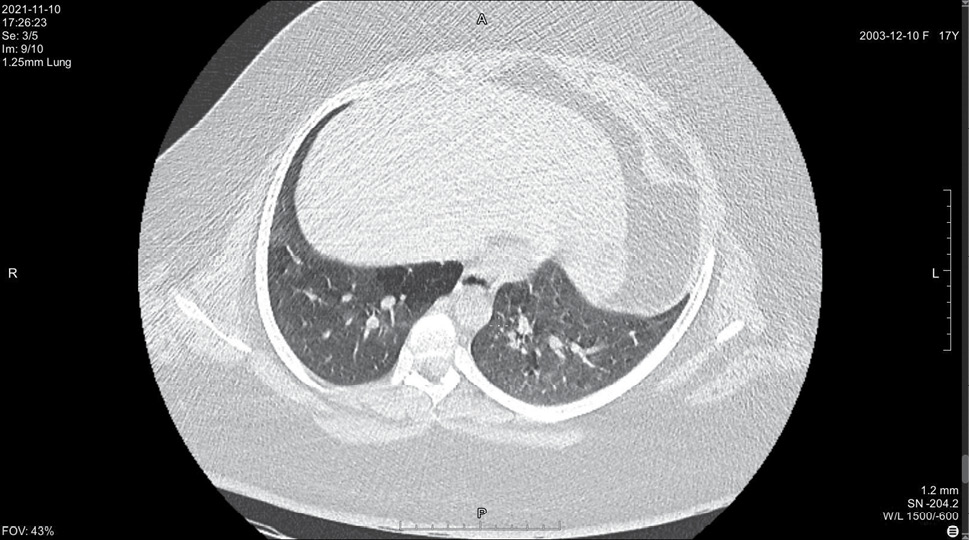

На 14 день болезни (10.11, 7 день госпитализации) была выполнена спиральная компьютерная томография грудной клетки, где выявлены признаки двусторонней интерстициальной полисегментарной пневмонии (рис. 1–8). Форма грудной клетки описана как обычная. Легочные поля расправлены. На томограммах бронхиальное дерево визуализировано до субсегментов: сами бронхи не деформированы, их просвет в пределах нормы, устья свободны, проходимость сохранена на всем протяжении. Во всех сегментах с обоих сторон определялись полиморфные, сливные участки уплотнения легочной ткани по типу матового стекла с участками консолидации. На этом фоне были видны просветы бронхов. Определялись фиброзные тяжи в проекции апикальной плевры обоих легких. Контуры диафрагмы четкие, синусы свободные, свободная жидкость в плевральной полости отсутствовала. Трахея обычной формы и размеров, карина острая. Сосудистые структуры верхнего средостения с четкими контурами и нормального диаметра, стенки сосудов без кальцинатов. Медиастинальные лимфоузлы и лимфоузлы корней обоих легких (без контрастного усиления) визуализированы единично, не увеличены. Сердце расположено обычно, размеры в пределах нормы. Выявлены умеренные дегенеративно-дистрофические изменения грудного отдела позвоночника. Мягкие ткани грудной клетки без особенностей. По заключению врача-рентгенолога, объем пораженной легочной паренхимы достигал 95%. Наиболее вероятно, что патологический процесс у пациентки имел вирусную природу.

Рисунок 5. Томограмма легких на уровне ThVII

Рисунок 6. Томограмма легких на уровне ThVIII